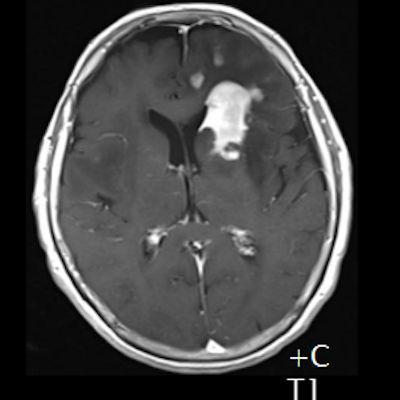

- (A) Her iki periventriküler beyaz cevherde aksiyel T2A, FLAIR serilerde hiperintens, T1A hipointens geniş ödem alanları (oklar) izlenmektedir. Sol frontalde T2A’da hipointens kitle lezyonuna (ok) dikkat ediniz.

- (B) Aksiyel postkontrast T1A görüntülerde büyüğü sol frontalde kontrastlanma gösteren multipl kitle lezyonları (oklar) izlenmektedir.

- Genellikle supratentoriyal alanda, bazal ganglion, periventriküler beyaz cevher, orta hat ve korpus kallozum vb. yerleşme eğiliminde tek veya multipl kitleler şeklinde görülür.

- Kitleler çoğunlukla solid ve homojendir.